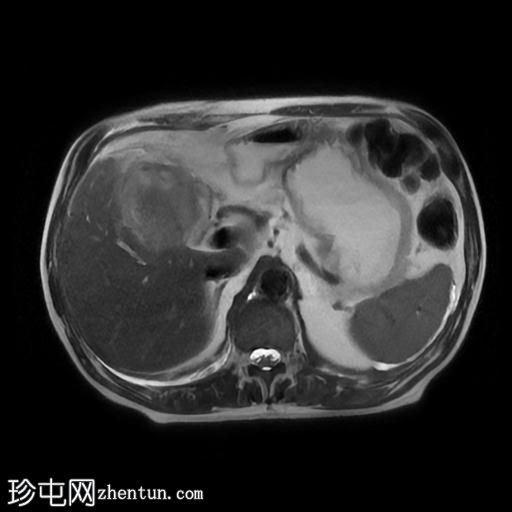

MRI

T2加权像

冠状位T2加权像

脂肪抑制像

胆囊切除术后,可见肝总管局部断裂,尤其是在胆囊管开口上方。该断裂伴有胆囊切除部位形成较大的血肿或胆汁瘤。

胆管损伤可能发生在手术过程中,导致胆汁渗漏到周围组织,从而形成血肿或胆汁瘤。这可能出现明显的临床症状,并可能需要进一步干预,具体取决于病情的严重程度和患者的临床表现。